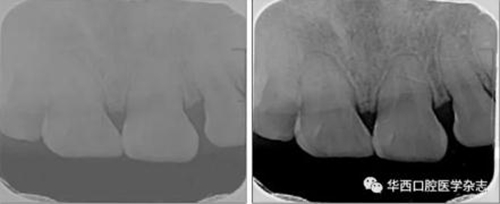

(2)X線片可調整灰度進行動態(tài)對比審閱。如圖2所示,同一張X線片經灰度調整后,清晰顯示根折影像。

左:疑似根折;右:可見明顯根折。

圖 2 X線片不同灰度值的對比結果